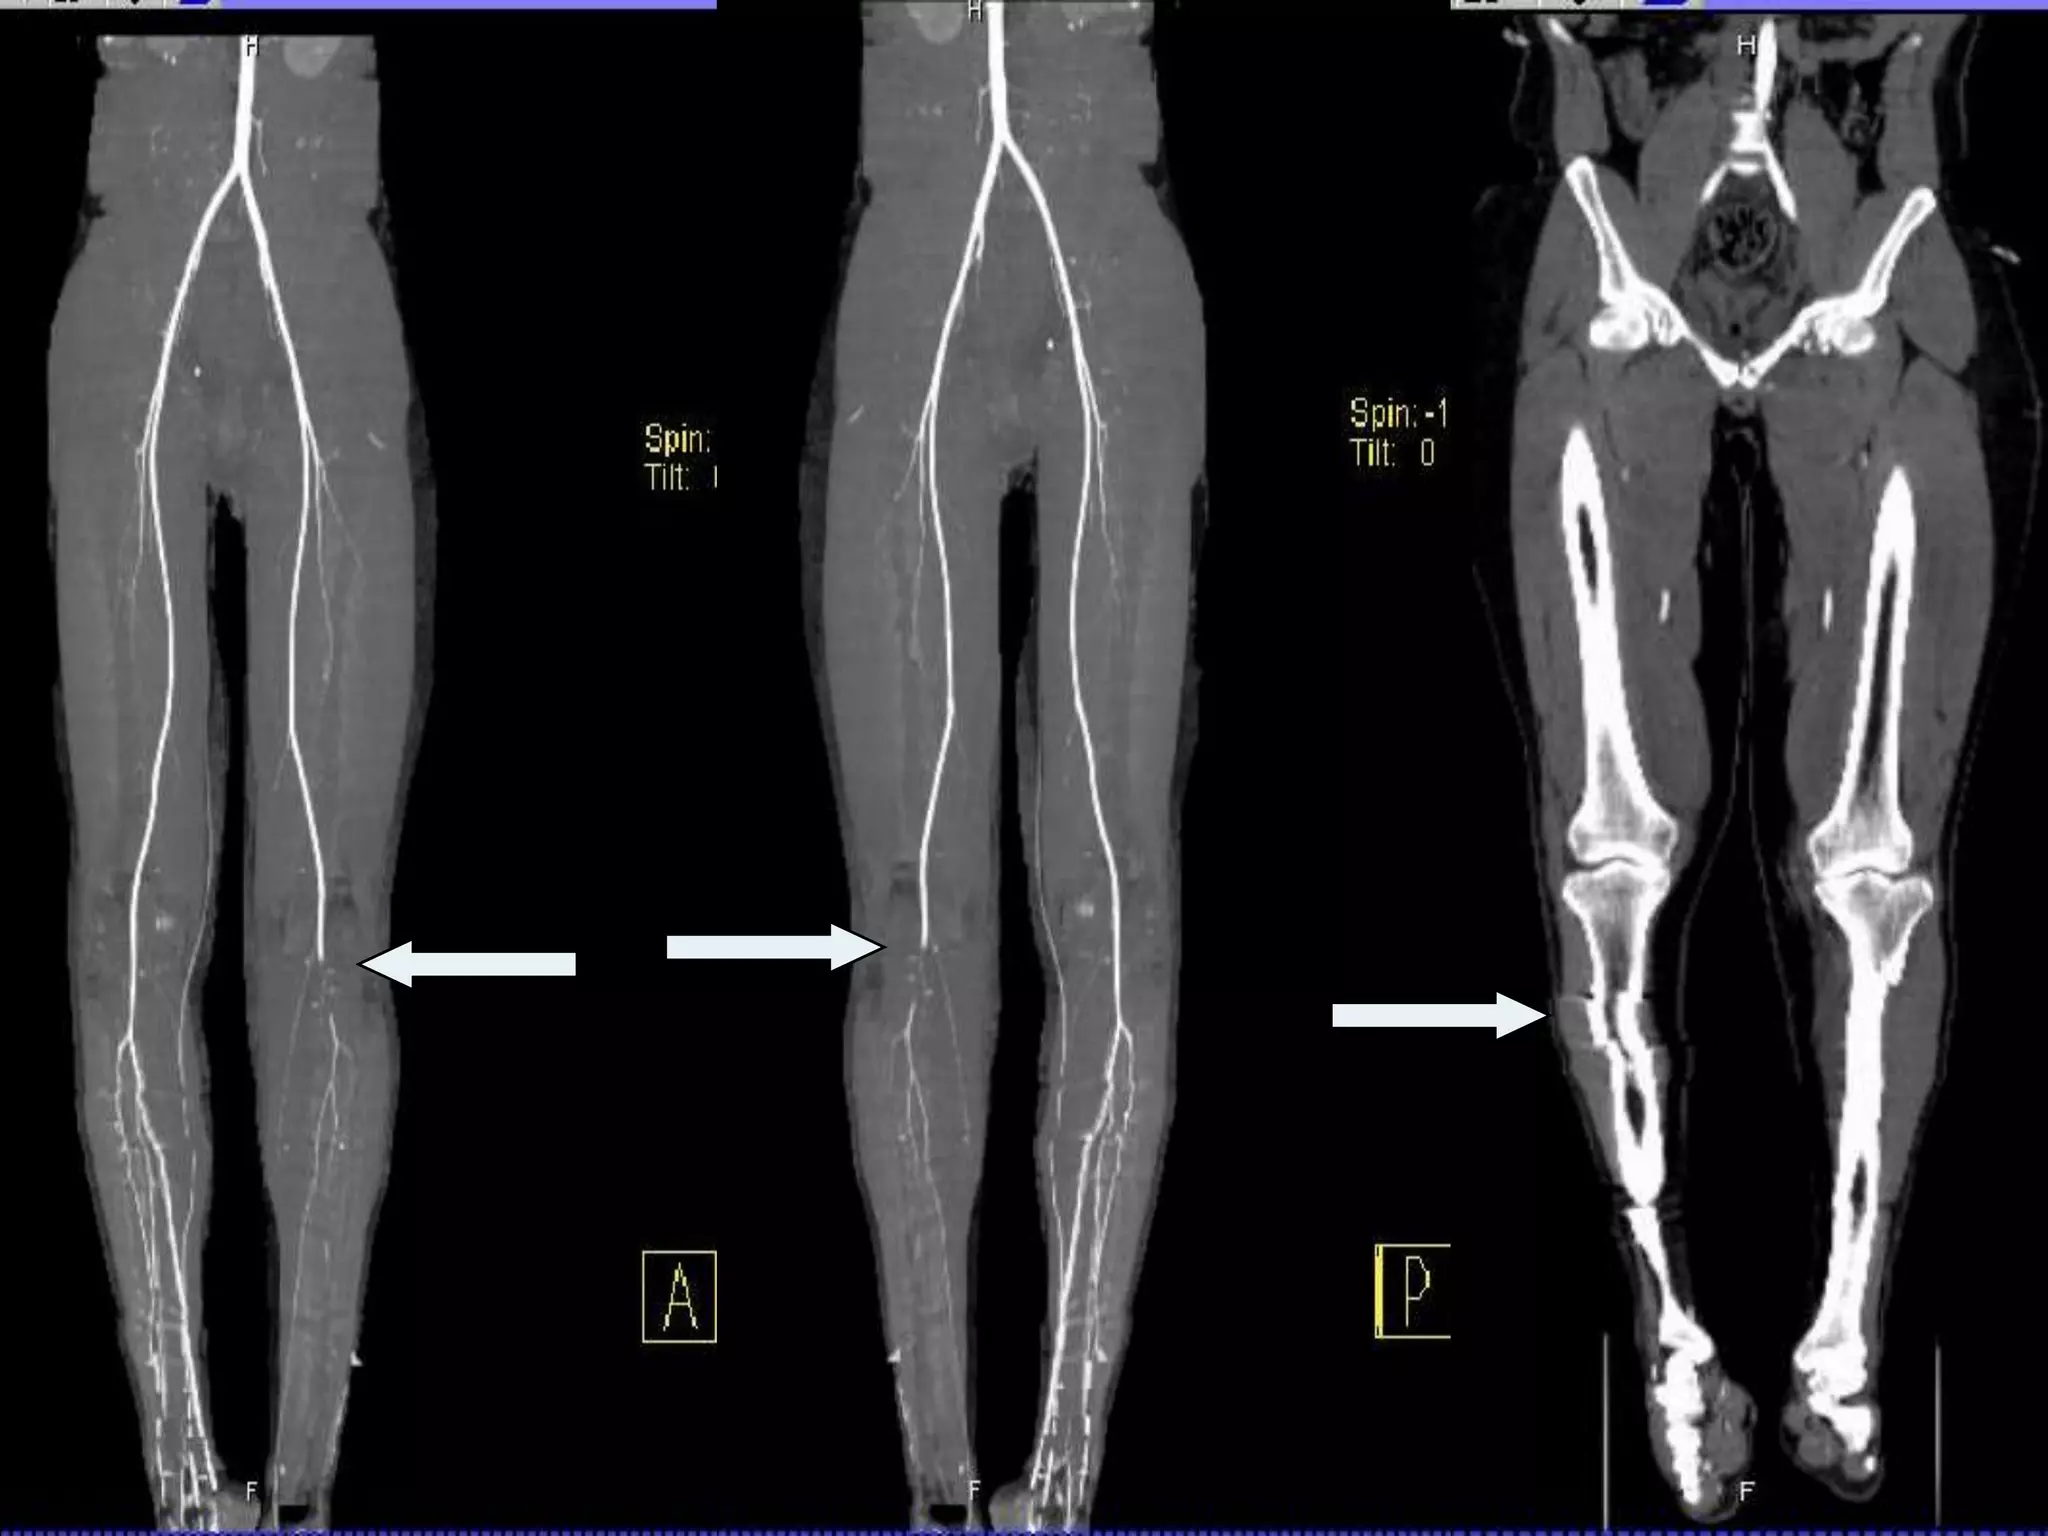

CT angiogram was doneIt showed Vascular injury @ the level of             segment 2 of the Popliteal arteryNo distal run off

CT angiogram wasdoneIt showed Vascular injury @ the level of segment 2 of the Popliteal arteryNo distal run off

Post OP Hehad arterial spasmConfirmed by CT angiogramHe recovered form the spasm in few hoursThe limb was warm with palpable pulsesBoth P.tibial & D.pedisWith good Doppler signalsTransferred to KFMC